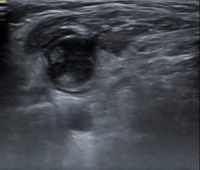

Abbildung 2: Fehlender Hilus. Dieser Lymphknoten weist keinen Hilus auf, alle anderen Kriterien sind jedoch erfüllt. Tumorzellen destruieren die reguläre Architektur des Lymphknotens und führen so zu einer Obliteration der Hilusstruktur. „Diffuse large B-cell lymphoma“ (DLBCL).